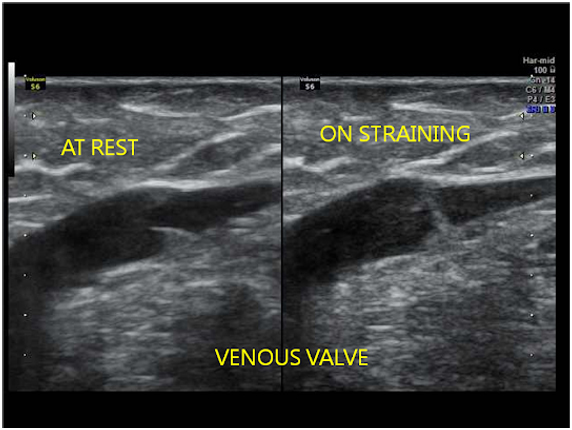

In the legs, veins have to carry blood upward against gravity. To make this possible, veins contain one-way valves that prevent blood from flowing backward.

The most common and reliable test to diagnose varicose veins is a Colour Doppler Ultrasound scan.

This is a safe, painless, non-invasive test that shows: